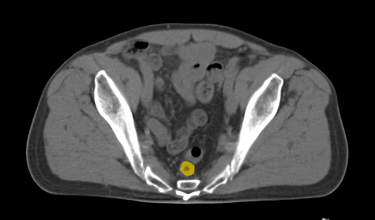

The DAM Contour features a comprehensive collection of OARs and CTVs that are ready for immediate use, without the need for manual creation of atlases or manual adjustment of data. This product includes all standard OAR and CTV structures (over 117 in total).

The Pelvis lymph node region encompasses lymph nodes that include the obturator lymph nodes, internal and external iliac lymph nodes (limited anteriorly at the level of the femoral heads), and extends up to the common iliac lymph nodes, covering the L5/S1 region.

Pelvis